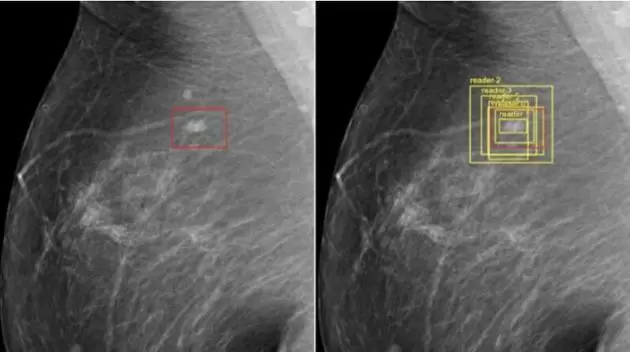

谷歌公司的研究人员已经成功训练出能够检测乳腺癌的人工智能,其准确率甚至比医生还高。

虽然IBM公司的人工智能“沃森”很早就介入医学了,但是今天说的就是谷歌的人工智能医疗计算,从目前谷歌公司人工智能对放射医学影像结果的判断上,其准确率比世界上最高的医生还要高出许多。当然这些数据大部分都是实验室的数据,具体的临床诊断会面临更复杂的情况和病理结果,还需要人工的干预和判断,人工智能现在最多只能算医疗辅助。